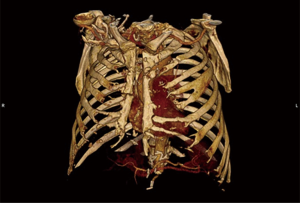

Indications for reconstruction of sternal non-union after sternotomy are relatively simple. These patients suffer from persisting symptoms of an unstable sternum such as pain and unpleasant movements even with minimal changing of the position of the body. Some of them previously underwent various interventions to repair the sternum and in the majority the sternum is almost completely destroyed (Figure 7) with a substantial gap and multiple fragments of broken wires.